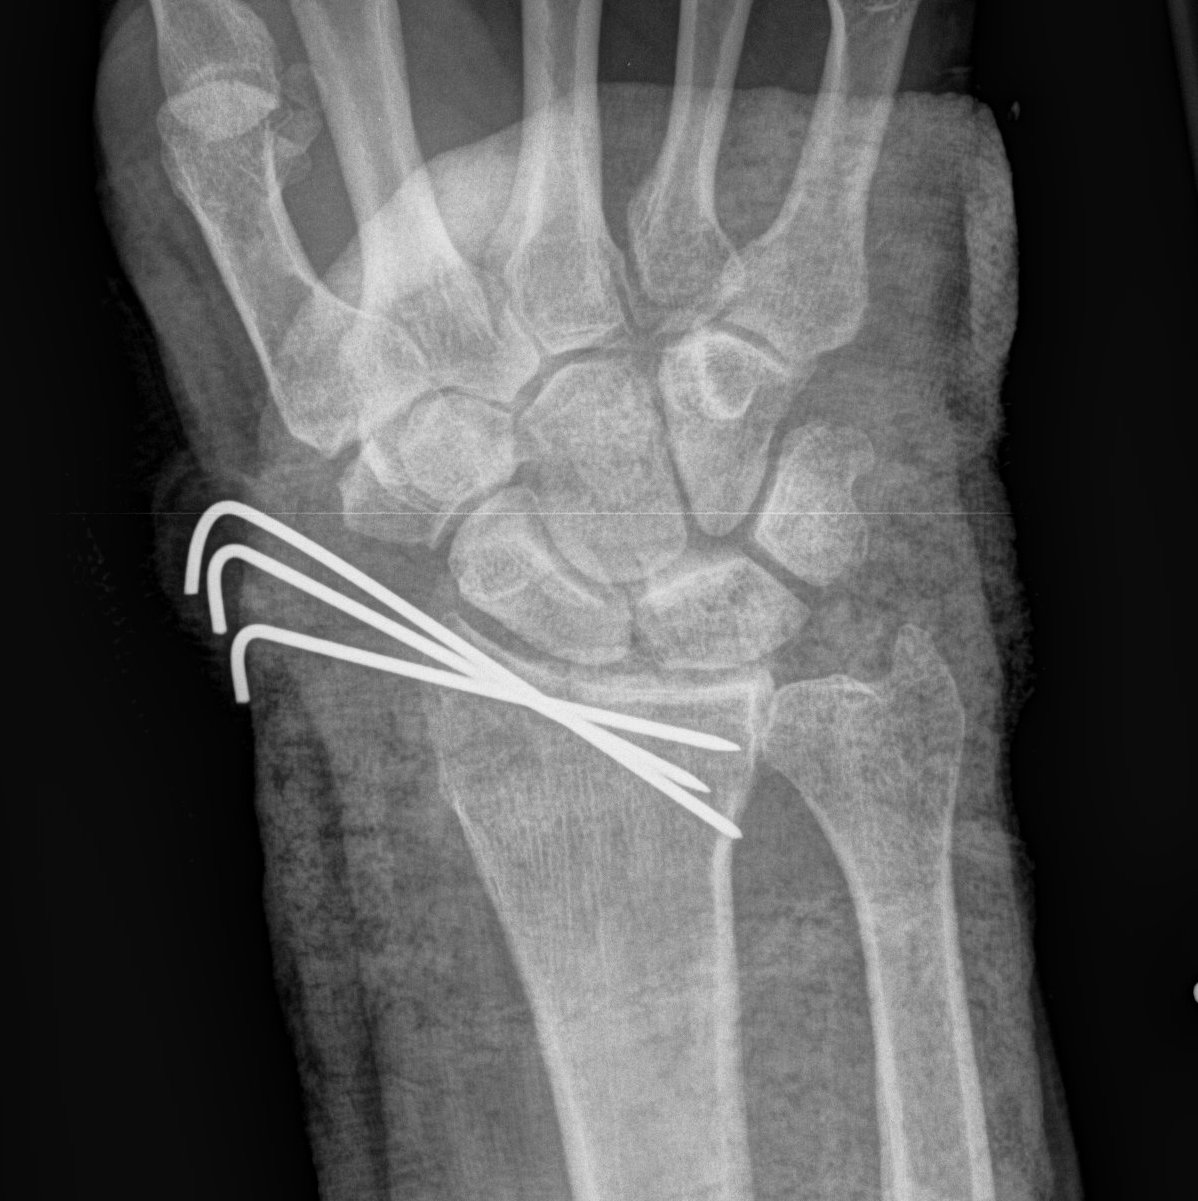

K wires

Distal Radius Fracture K wires APplateex fixbridge plate

K wires v Volar locking plates

Francheschi et al Br Med Bull 2025

- systematic review of K wires v volar locking plates

- 14 studies and 1300 patients

- better DASH outcome scores with locking plates

- increased cost and surgical times with locking plates